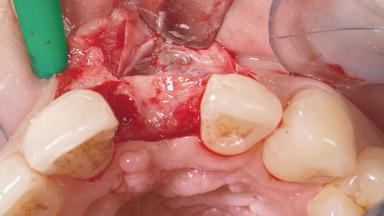

A 30-year-old female patient had lost tooth 21 and was referred to our clinic for consultation and treatment. Due to advanced apical infection, tooth 21 had been extracted two months earlier at another clinic and an acrylic-resin tooth had been bonded to the adjacent teeth. The patient desired implant treatment to avoid any damage to the adjacent natural teeth. While the patient had no history of any systemic disorder, she was a heavy smoker and exhibited medium to advanced periodontitis in the entire jaw. After the initial treatment to achieve a pocket probing depth of less than 4 mm and no bleeding on probing, a decrease in the height of the papillae mesial and distal to the extraction site and overall gingival recession were observed.

Bone Augmentation Horizontal|Staged

Augmentation Materials Autogenous chips|Membrane

Bone Volume Deficient horizontally, requiring prior grafting